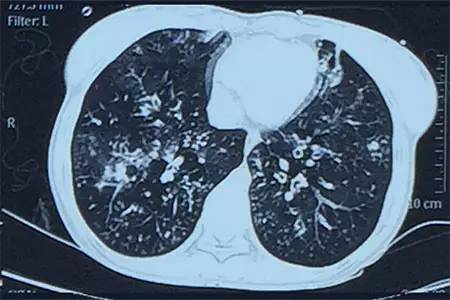

肺CT見(jiàn)下圖

該患者肺部影像學(xué)表現(xiàn)為明顯的支氣管擴(kuò)張,同時(shí)伴有彌漫的滲出斑片影,考慮合并感染,細(xì)菌學(xué)培養(yǎng)提示為綠膿桿菌,結(jié)合藥敏結(jié)果給予頭孢他啶+阿米卡星抗感染,患者存在II型呼吸衰竭予氣管插管機(jī)械通氣支持,加強(qiáng)體位引流排痰,治療18天,患者情況好轉(zhuǎn)出院。